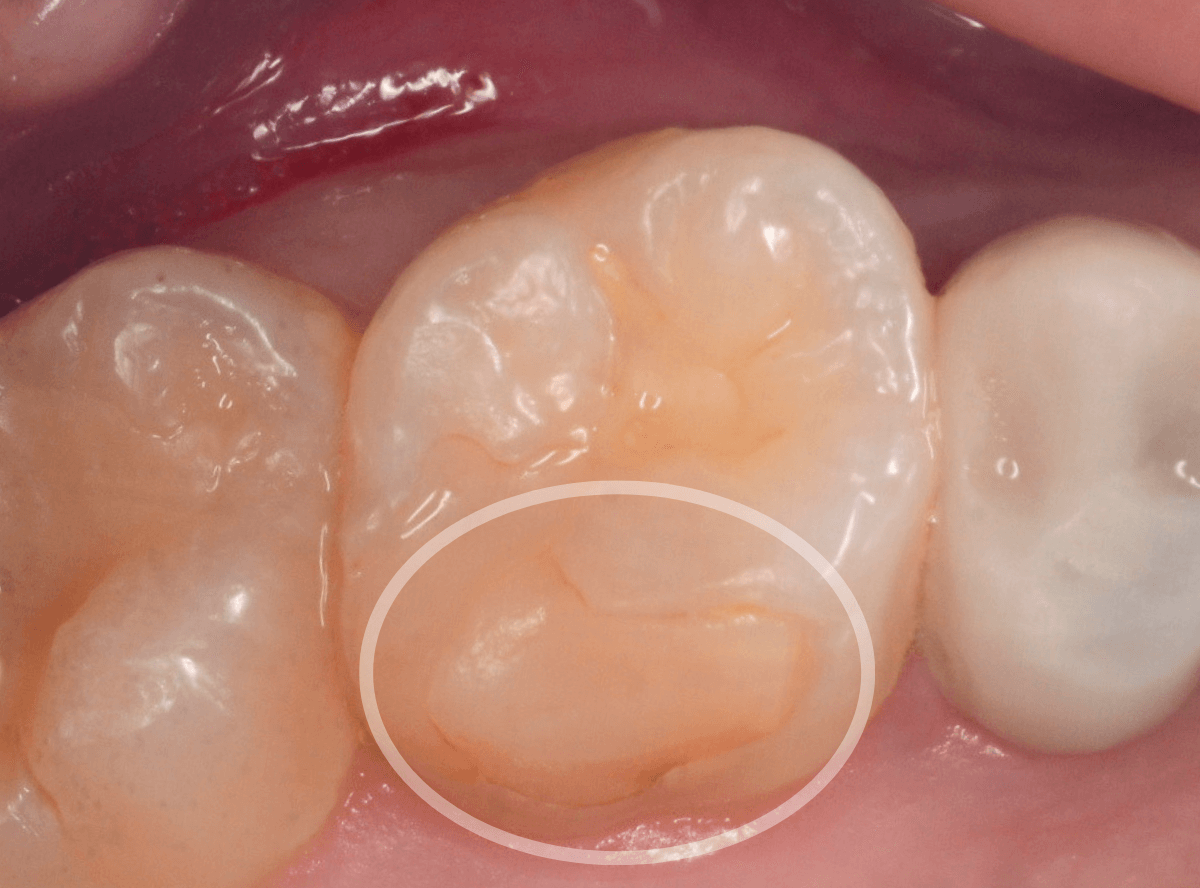

Case.18 虫歯なのは間違いないが、境界がはっきりしない

「つめものが外れて、噛むと痛い」という訴えで来院された患者さんさんです。

一見で、表面が虫歯になっているのと、レジンが劣化しているのがわかります。

レントゲン写真で確認します。

〇部が当該の歯です。

症状もあるので、虫歯が深そうですが、全体がもやっとして、どこからどこまで虫歯なのかはっきりわかりません。

まれに、こんな時もあります。

レジンを外し、虫歯の処置を進めます。

慎重に虫歯を除去し、一安心か、という寸前で(〇部、小さく出血しているところ)露髄してきました。

神経を除去しないとダメかもしれません。。。

神経を保護するお薬をつめて、経過観察します。

痛みが出ませんように。。。